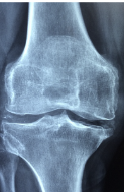

다리 관절 통증의 증상은 다음과 같습니다.

- 통증: 다리 관절 주변이나 관절 자체에서 통증이 발생할 수 있습니다. 또한, 통증은 적절한 치료 없이 지속될 경우 더 심해질 수 있습니다.

- 뻣뻣함: 다리 관절이 뻣뻣하거나 어색해지는 느낌이 들 수 있습니다.

- 감각 이상: 다리 관절 주변의 감각이 둔해지거나, 저하되는 느낌이 나타날 수 있습니다.

- 걷기가 힘들어짐: 다리 관절 통증이 심해지면 걷기가 어려워질 수 있으며, 보행이 저하될 수 있습니다.

- 관절 부종: 다리 관절 주변에 부종이 발생할 수 있습니다.

- 열감: 다리 관절 부위에서 열감이나 열이 발생할 수 있으며, 염증이 있을 때 나타나는 증상입니다.

위와 같은 증상이 나타나면 즉시 전문가의 진료를 받는 것이 좋습니다. 초기에 치료를 받을 수록, 증상의 호전이 빠르고 덜 심각할 가능성이 높습니다.